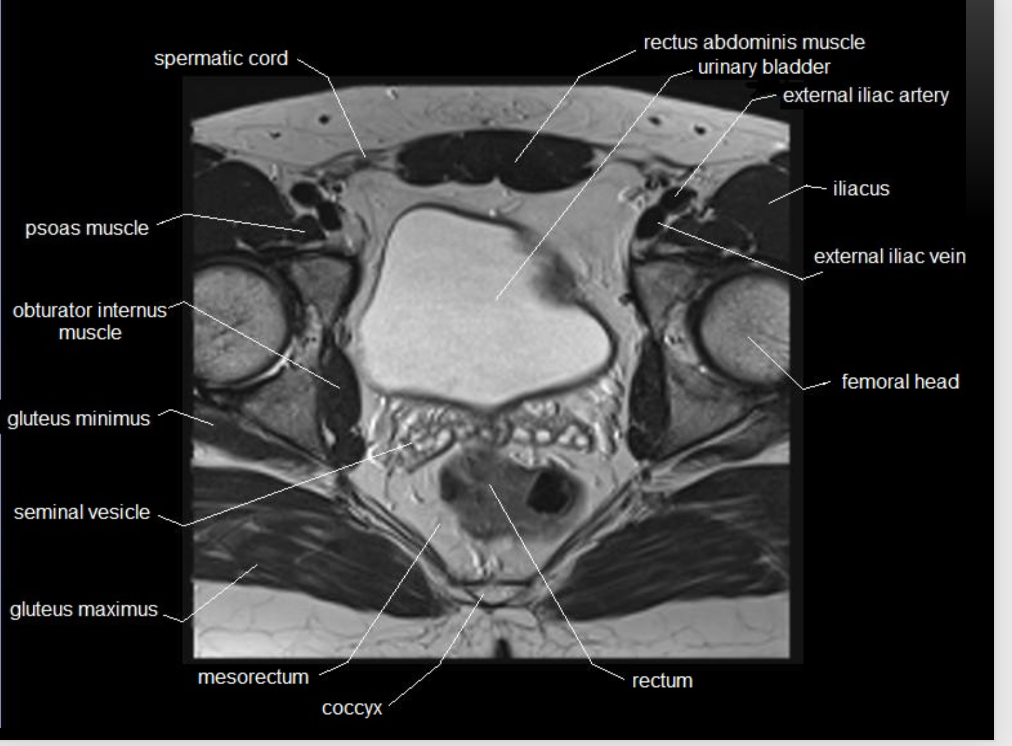

What type of imaging modality is this & fill in the blanks

MRI prostate, axial